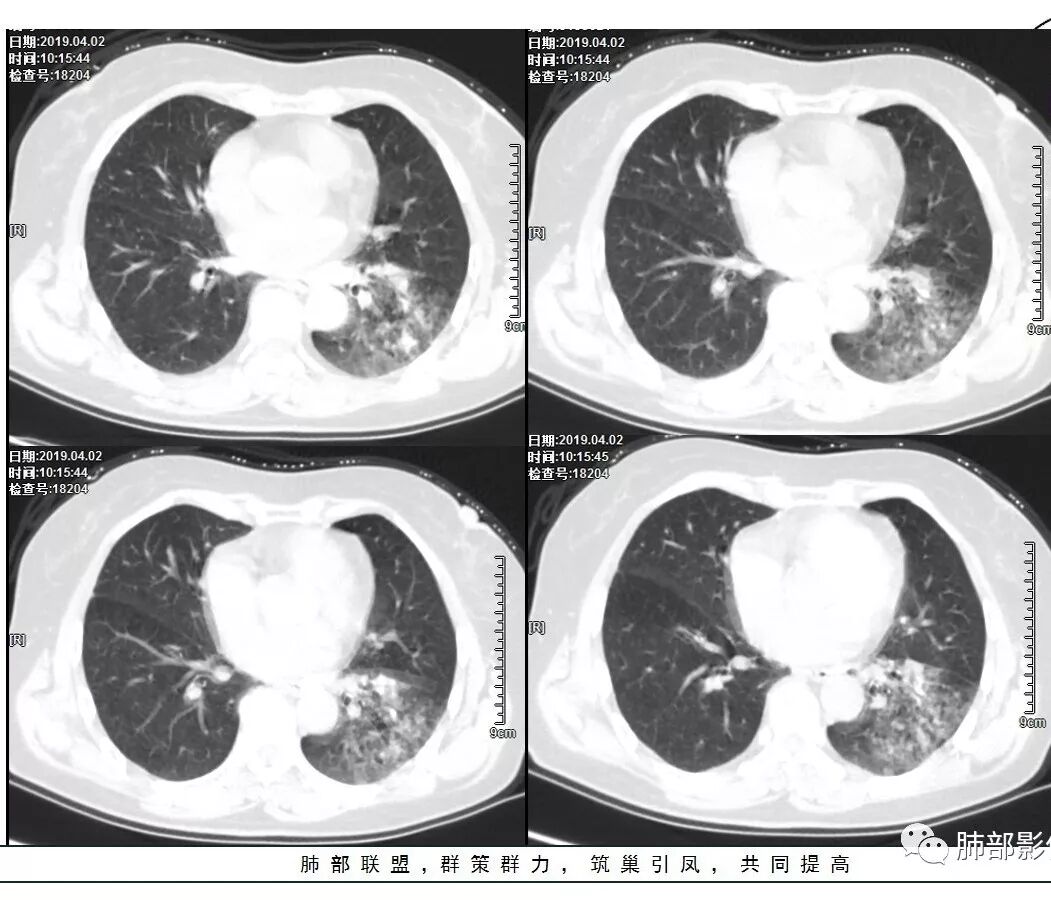

胸CT:左下叶实变影及磨玻璃影,小叶间隔增厚,内部支气管扩张、僵直。左肺门淋巴结肿大、钙化。考虑肺腺癌?合并感染

胸CT:左下叶基底段支气管狭窄,沿支气管分布斑片实变影、网格影、磨玻璃影,支气管充气征,无重力效应,左肺门淋巴结肿大、钙化。

左下叶实变影及磨玻璃影,内部支气管扩张、僵直。纵膈肺门淋巴结钙化。balf结核杆菌核酸阳性。

2.左肺下叶片状影及多数有边界的结节影,较散,多形性,密度不均(注意许多老师提到这个特点还是比较明显的)。左肺下叶体积未见缩小。

3.病灶强化比较明显。

4.左下叶支气管壁增厚,管腔不均匀狭窄,没有堵塞

5.肺门纵隔见增大钙化淋巴结。提示曾经存在慢性病损可能。